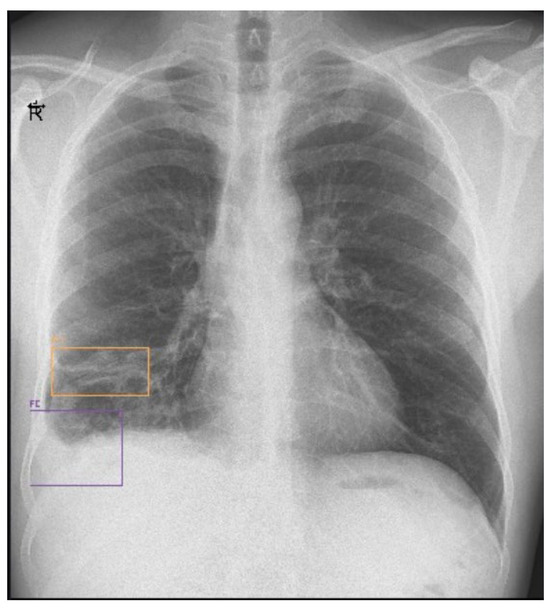

On the seventh day of hospitalization, the patient’s condition worsened and he began to exhibit chest pain, recurrence of fever after 4 days of being afebrile, and right basal subcrepitant rales. A chest X-ray was performed, which showed an inhomogeneous opacity (3.8/3.7 cm) on the lower right lobe and a residual inhomogeneous opacity on the upper left lobe (Figure 1). Biological tests showed leukocytosis (31.910 cells/mm3) with neutrophilia (81.3%) and lymphopenia (7%), an inflammatory syndrome (erythrocyte sedimentation rate (ESR) = 27 mm/1 h, fibrinogen = 507 mg/dL, procalcitonin = 12.27 ng/mL), a syndrome of nitrogen retention (creatinine = 1.91 mg/dL, urea = 107 mg/dL), and a CD4 count = 395 cells/mm3. The patient received antibiotic treatment with Meropenem 1 g/12 h (empirical treatment for bacterial suprainfection; creatinine clearance = 48 mL/min) and the initial antiretroviral therapy was replaced with Bictegravir/Emtricitabine/Tenofovir Alafenamide (for regimen simplification).

Figure 1. Chest X-ray (day 7).